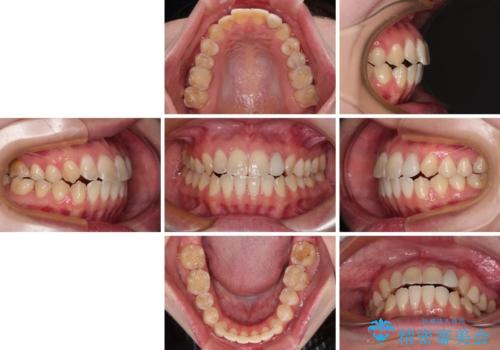

開咬を治す インビザラインによる矯正治療

- 上下前歯の開咬を気にして来院された患者様です。

開咬はインビザラインを用いると有意に改善ができるため、インビザラインによる矯正治療を行うこととしました。

途中1年8ヶ月ほど来院されず、久しぶりの来院後は治療が面倒とのことで、前歯の叢生や隙間に不十分な点が残った状態での終了となりました。